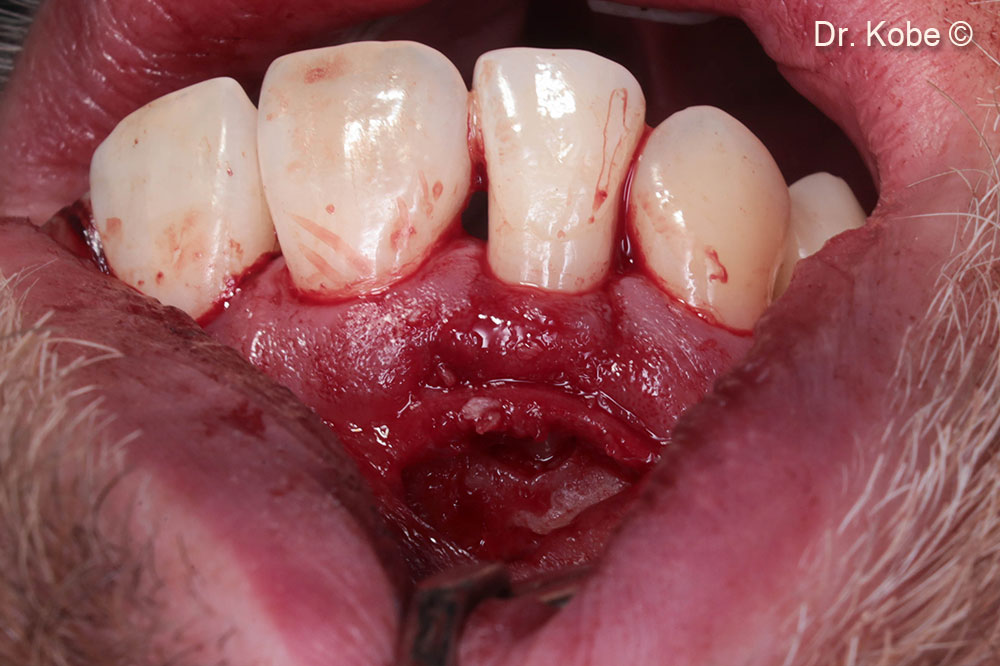

Rạch ngang (NIPSA) ở tiền đình

Truy cập vào lỗi

Khuyết tật được lấp đầy bằng Gen-OS

Vết thương được khâu bằng các mũi khâu gián đoạn